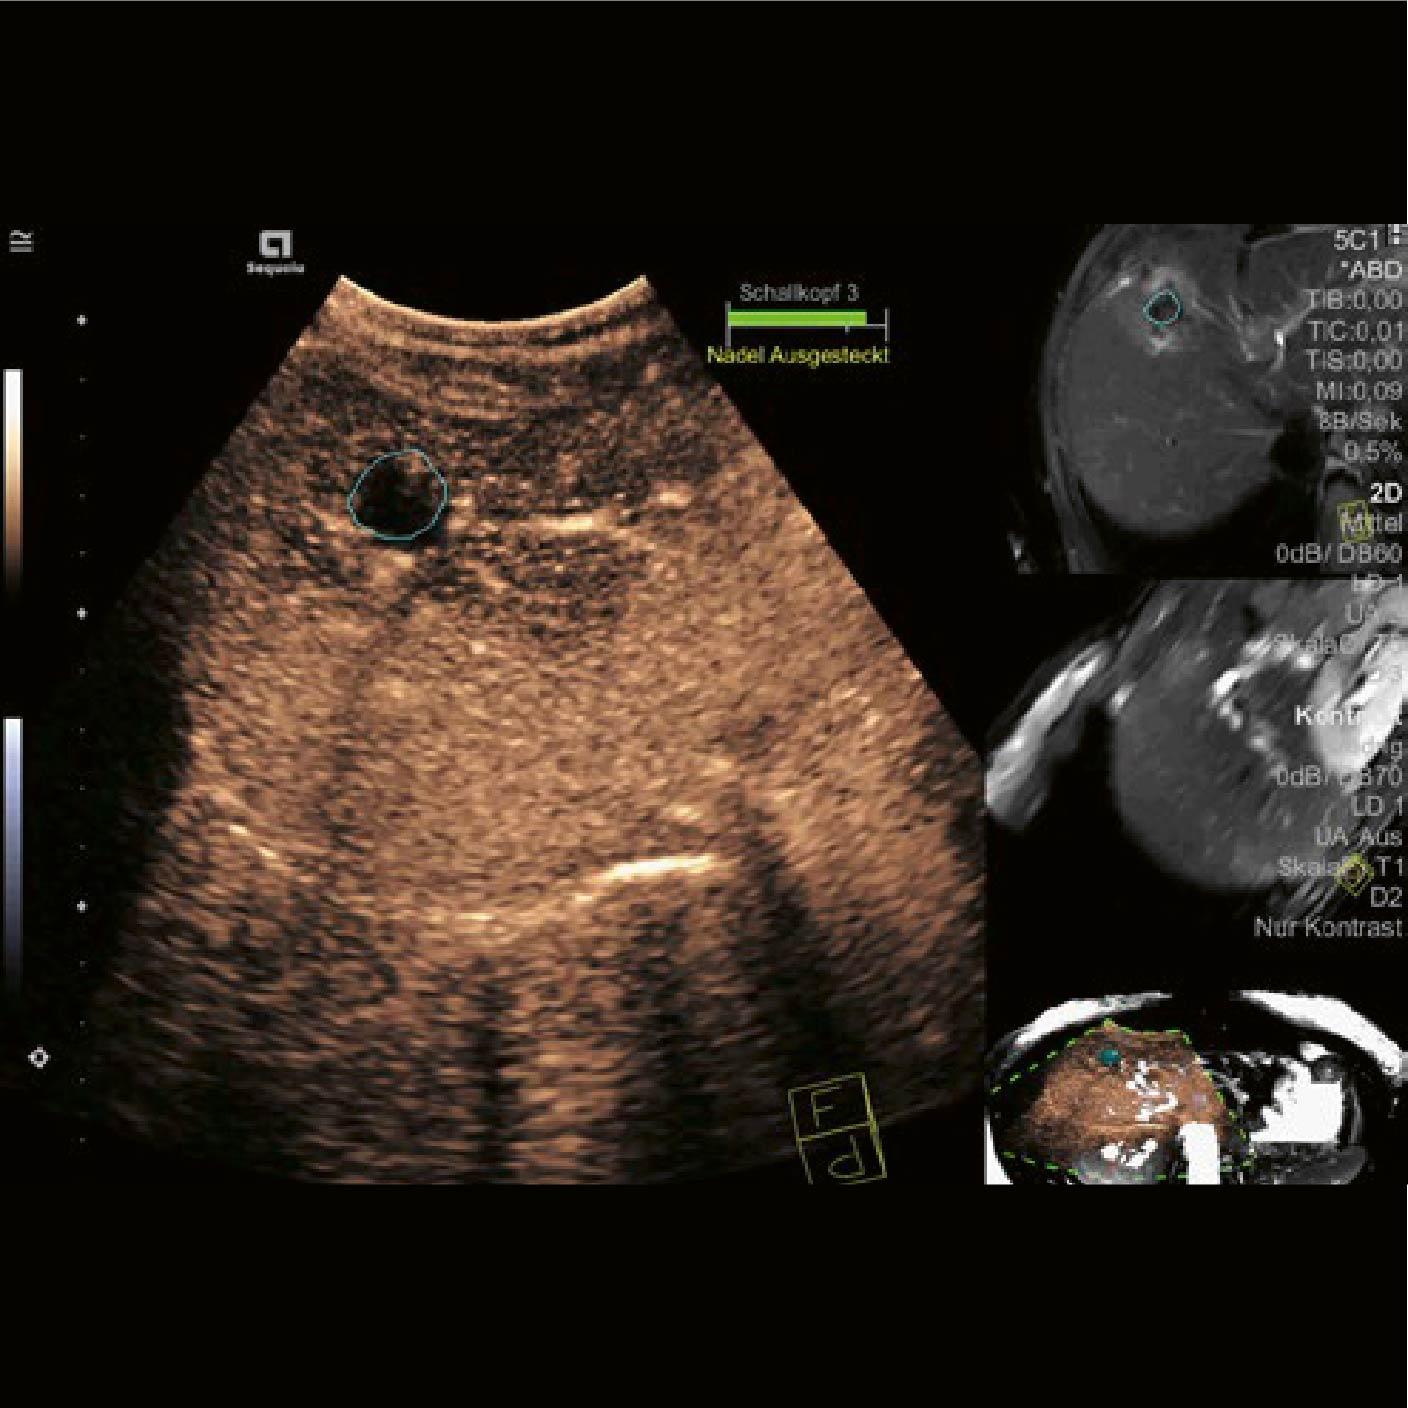

Se realizó una ecografía 2D de la región de interés (ROI). Además de los clips quirúrgicos, previamente identificados en el área tratada, la ecografía mostró parénquima hepático con baja conspicuidad en comparación con el tejido circundante [Fig. 1].

Las imágenes de la RM fueron cargadas en el sistema ACUSON Sequoia y se activó la tecnología de Fusión. Durante la fase de planificación, se utilizó segmentación automática para alinear de manera eficaz el área tratada [círculo azul Fig. 2].